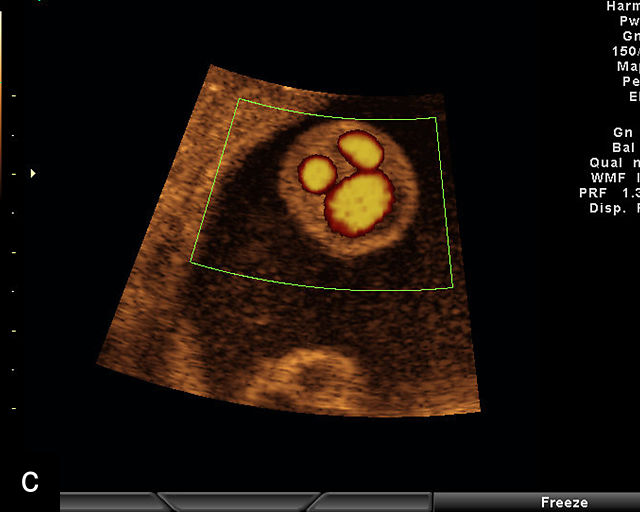

The umbilical cord serves as the lifeline connecting the fetus to the placenta. It arises from the midportion of the fetal abdomen and typically inserts into the center of the placenta (Figure 16). The average length of the umbilical cord is approximately 55 cm (22 inches).185 It contains three vessels: two arteries, which originate from the fetal left and right internal iliac arteries, and one vein, collectively referred to as a three-vessel cord.

16

Normal appearance of the umbilical cord with two umbilical arteries and a single vein. (a–c) Cross-section of the umbilical cord on grayscale (a,b) and power Doppler (c) ultrasound. In the normal cord, three vessels are visible: a larger umbilical vein and two smaller umbilical arteries. This characteristic appearance is often referred to as the 'Mickey Mouse' sign, the larger circle (umbilical vein) representing Mickey’s face while the smaller circles (arteries) form his ears. (d–g) Grayscale (d) and color Doppler (e–g) images of transverse section of the lower fetal abdomen showing the two umbilical arteries diverging around the fetal bladder. (h) Longitudinal ultrasound view with color Doppler of a normal umbilical cord showing three vessels present in each coil: two arteries with flow in one direction and a single vein with flow in the opposite direction.

At a minimum, the mid-trimester ultrasound should include identification and documentation of the umbilical cord's fetal and placental insertions, as well as the number of cord vessels.66,186,187 In a transverse grayscale section of the cord, the two umbilical arteries can be visualized alongside the larger, thinner-walled umbilical vein, creating a characteristic ‘Mickey Mouse’ appearance (Figure 16a–c). Additionally, in a transverse section of the lower fetal abdomen, the umbilical arteries are seen encircling the fetal bladder. This can be seen on grayscale ultrasound and confirmed with color flow Doppler (Figure 16d–g).